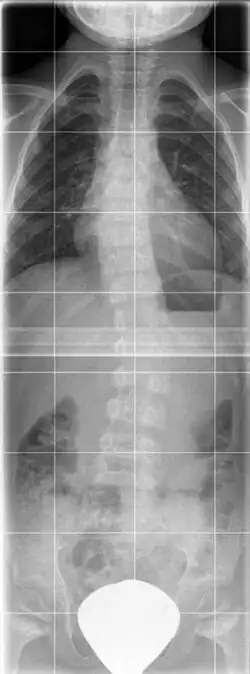

Rö-Aufnahme eines 7 j. Mädchens mit Spondylometaphysärer Dysplasie Typ Koslowski mit deformierten Femurmetaphysen und mäßiger Platyspondylie

Im Röntgenbild findet sich eine generalisierte Platyspondylie, die verkürzten Röhrenknochen weisen eine Deformierung der Metaphyse hauptsächlich am Schenkelhals und der Trochanteren auf, häufig besteht eine Coxa vara.[2]